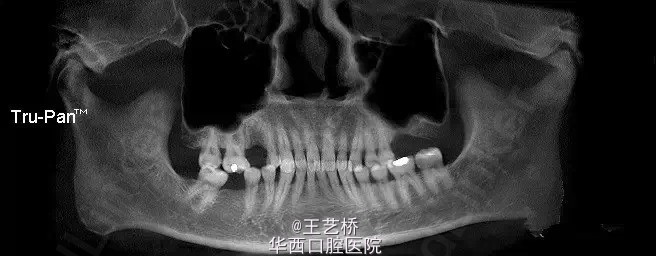

各式各样形态的上颌窦(二)

接着之前放图